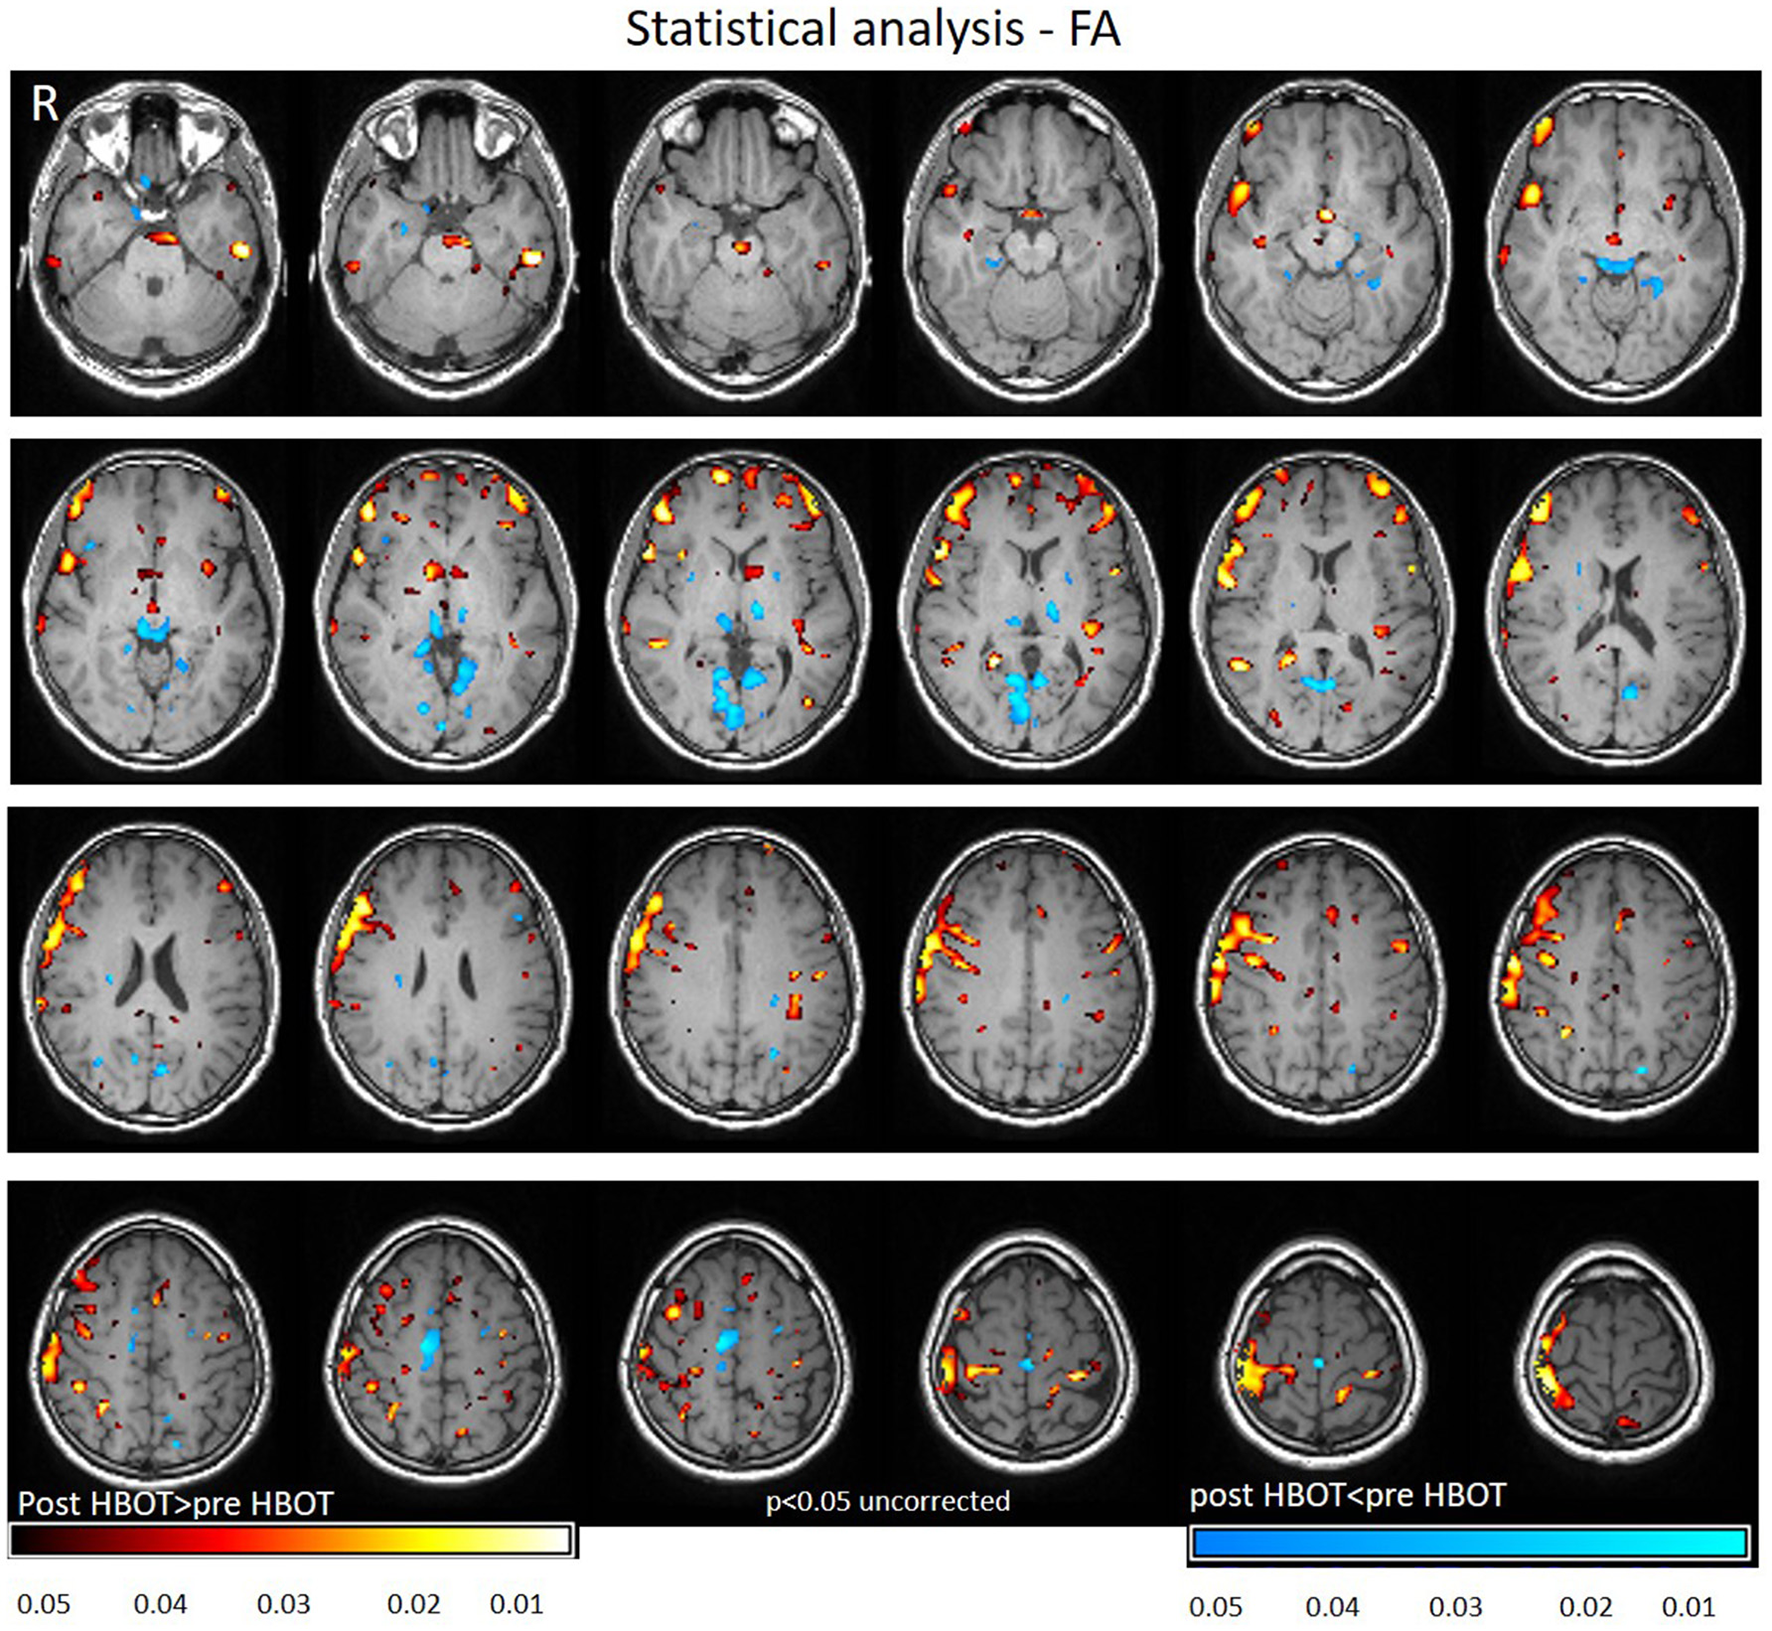

Voxel-based DTI analysis was compared before and after HBOT using paired t-test. FA and MD whole brain maps are depicted in Figures 2, 3, and show the statistically significant increase in FA (yellow in Figure 2) and decrease in MD (blue in Figure 3) average values.

Figure 2

Average DTI normalized delta change in FA maps. Yellow and red areas show a statistically significant increase in FA (p < 0.05).

Statistically significant increase in FA was found in regions related to motor function (internal capsule, midbrain), association fiber tracts inferior fronto-occipial fasciculus (IFOF), inferior longitudinal fasciculus (ILF), superior longitudinal fasciculus (SLF), Cingulum and in the genu of the Corpus Callosum.

Decrease in FA was found in areas related to the visual system (superior colliculi, calcarine sulcus) and other cognitive areas (thalamus, and posterior cingulate gyrus). Graphs of FA in significant clusters are presented in Figures 4A,B.